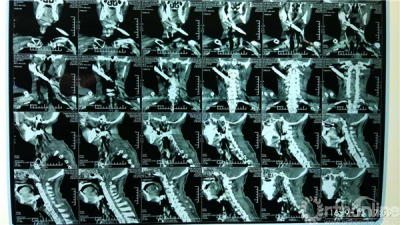

术前CT

多学科会诊后决定手术由经验丰富的夏天副教授主刀、卿湘城博士担任一助,刘国辉教授全程负责协调和技术监管,夏教授术中探查发现钢筋左侧将颈动脉鞘穿破,离颈总动脉仅数毫米,于颈椎前咽后壁穿破咽部,对侧斜向上跨过颈总静脉前方,穿破右侧腮腺穿出皮肤。为防止钢筋在取出过程中进一步损伤周围组织,夏天教授将钢筋套上胸管,最终顺利取出钢筋。耳鼻喉科乐建新、孙宇教授团队随后带领周涛博士将双侧咽后壁、右侧腮腺进行缝合,术后转至耳鼻喉科进一步治疗。目前患者生命体征平稳,四肢活动良好。